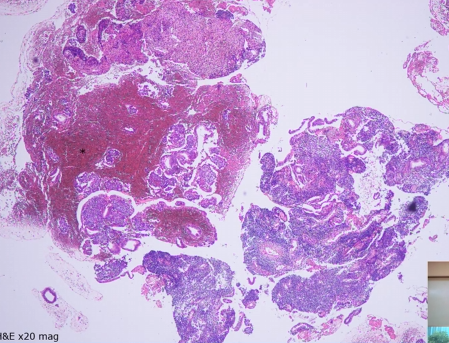

Endometrial Curretage

A

Fragmented specimen

Haemorrhage

You’re looking for normal structure (endometrial glands, simple columnar epithelium etc.)